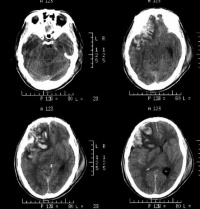

外伤性进展性颅内出血病变

原发性脑挫裂伤一般不需要手术治疗,但当有继发性损害引起颅内高压甚至脑疝形成时,则有手术之必要。对伴有颅内血肿30ml以上、CT示有占位效应、非手术治疗效果欠佳时或颅内压监护压力超过4.0kPa(30mmHg)或顺应性较差时,应及时施行开颅手术清除血肿。对脑挫裂伤严重,因挫碎组织及脑水肿而致进行性颅内压增高,降低颅压处理无效,颅内压达到5.33kPa(40mmHg)时,应开颅清除糜烂组织,行内、外减压术,放置脑基底池或脑室引流;脑挫裂伤后期并发脑积水时,应先行脑室引流待查明水原因后再给予相应处理。

对脑挫裂伤与脑震荡可以作出明确的鉴别诊断,并能清楚地显示脑挫裂伤的部位、程度和有无继发损害,如出血和水肿情况。同时,可根据脑室和脑池的大小、形态和移位的情况间接估计颅内压的高低。尤为重要的是,对一些不典型的病例,可以通过定期CT扫描,动态地观察脑水肿的演变或迟发性血肿的发生。近年来,在有此设备的医院CT已作为急性头伤的常规检查,因为单靠伤史和查体难以作出超早期诊断。Stein等(1990)指出在GCS13~15危害较小的轻型头

伤中,首次CT的阳性发现率竟占18%,并有5%需行手术治疗,强调早期CT检查的必要性。